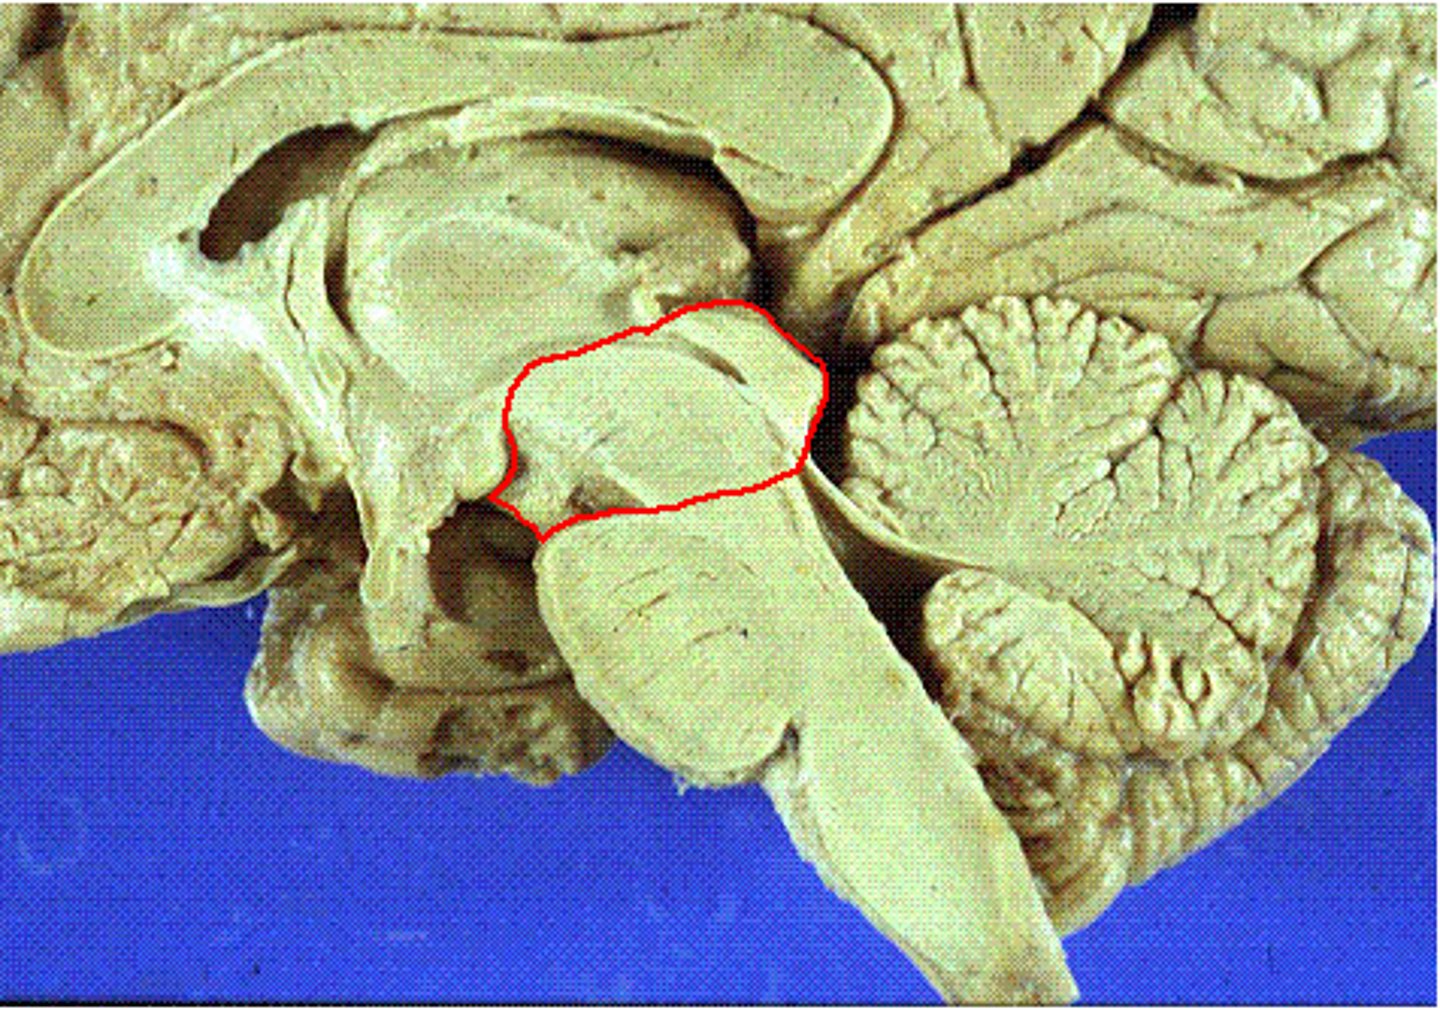

midbrain

or mesencephalon extends from pons to diencephalon. the pons is the center structure of the brain stem, located between the midbrain and the medulla oblongata

tectum of midbrain

superior and inferior colliculi

tegmentum of midbrain

involved in movement and arousal

cerebral peduncles

located on the ventral surface of midbrain. has corticospinal tract (voluntary movements) & corticobulbar tracts (motor control of face & head)